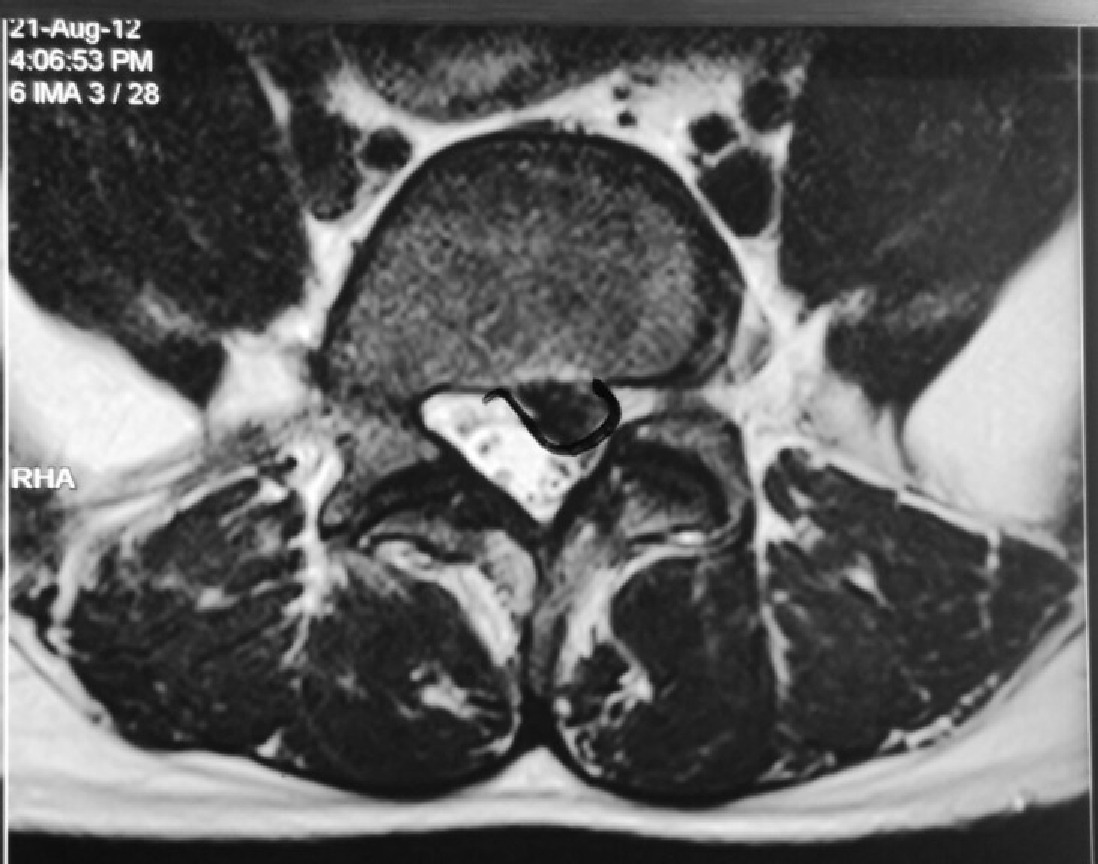

This is a patient who presented with sciatica in his left leg from a L5/S1 posterolateral left sided slipped disc in 2012.

He was offered surgery but chose conservative treatment.

His pain eventually resolved over a period of 3 to 6 months after taking medications and undergoing intensive physiotherapy.